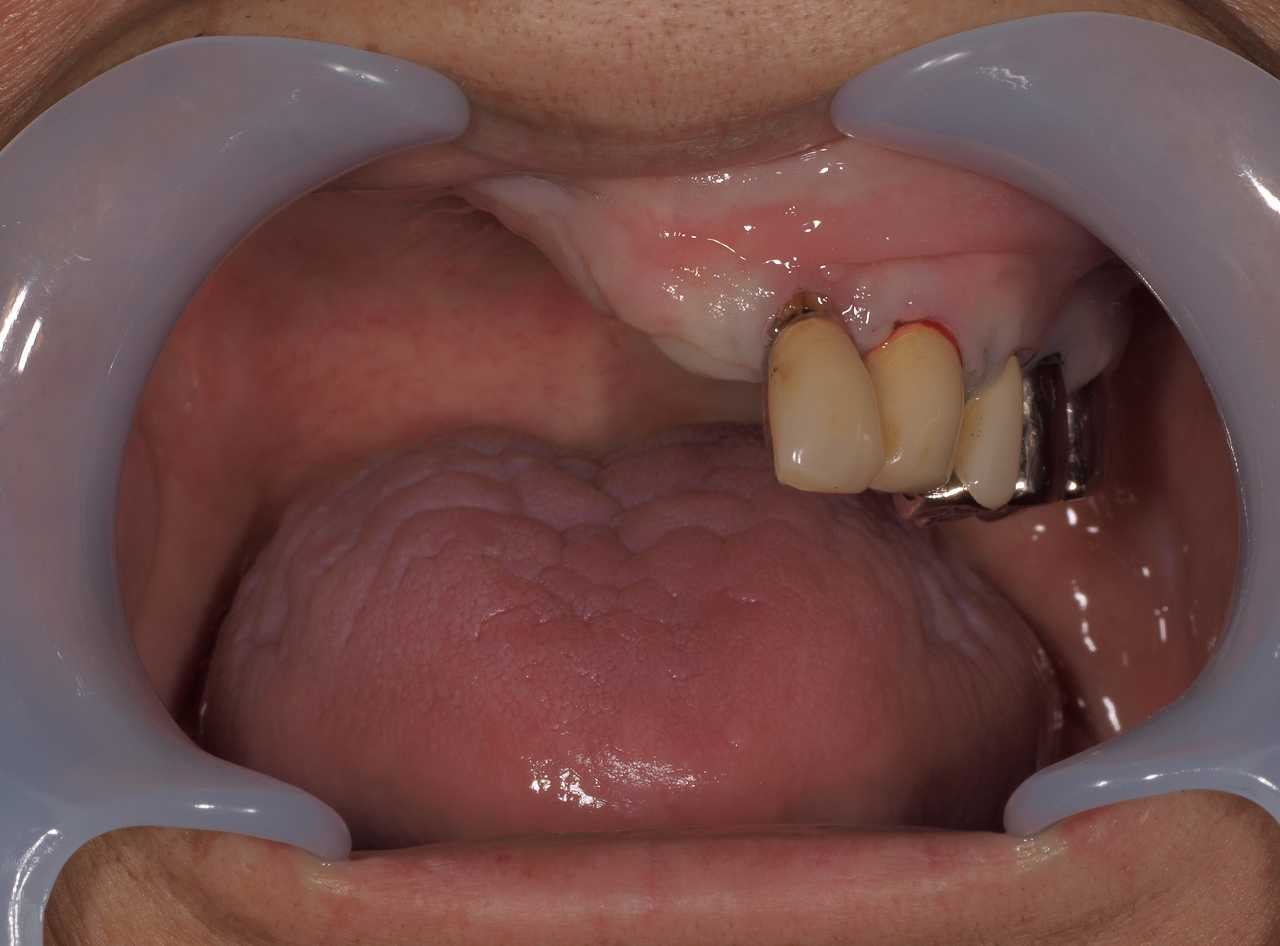

前歯がグラグラする 診てほしい 60台男性 入れ歯使用

前歯がグラグラする 診てほしい 60台男性 入れ歯使用

残存歯になります

下顎も入れ歯を使用していますが、、、